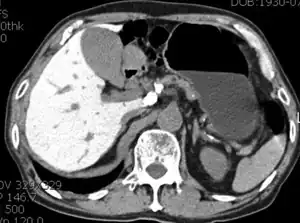

Abnormal liver enzyme results are common in patients on amiodarone. Much rarer are jaundice, hepatomegaly (liver enlargement), and hepatitis (inflammation of the liver).[31]

Low-dose amiodarone has been reported to cause pseudo-alcoholic cirrhosis.[32][33]